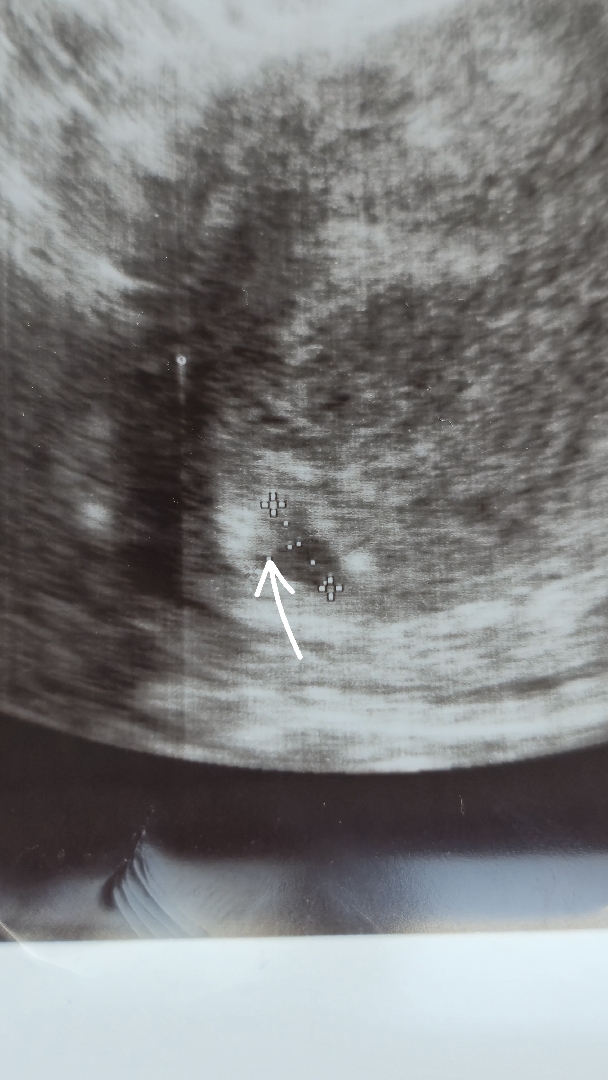

춈파사진에 난황 보이는지 같이 봐주세요 !

이거 난황 맞을까요? 담당원장님은 아기집만 보인다고 하셨는데 집에 와서 춈파사진 보니 제 눈에만 난황이 보이는건지... 아님 이게 난황이 아닌건지 싶어서요🥲

주수에 따라 다를텐데 아기집 막 생기기 시작한거면 난황 아닐 확률이 더 높아요